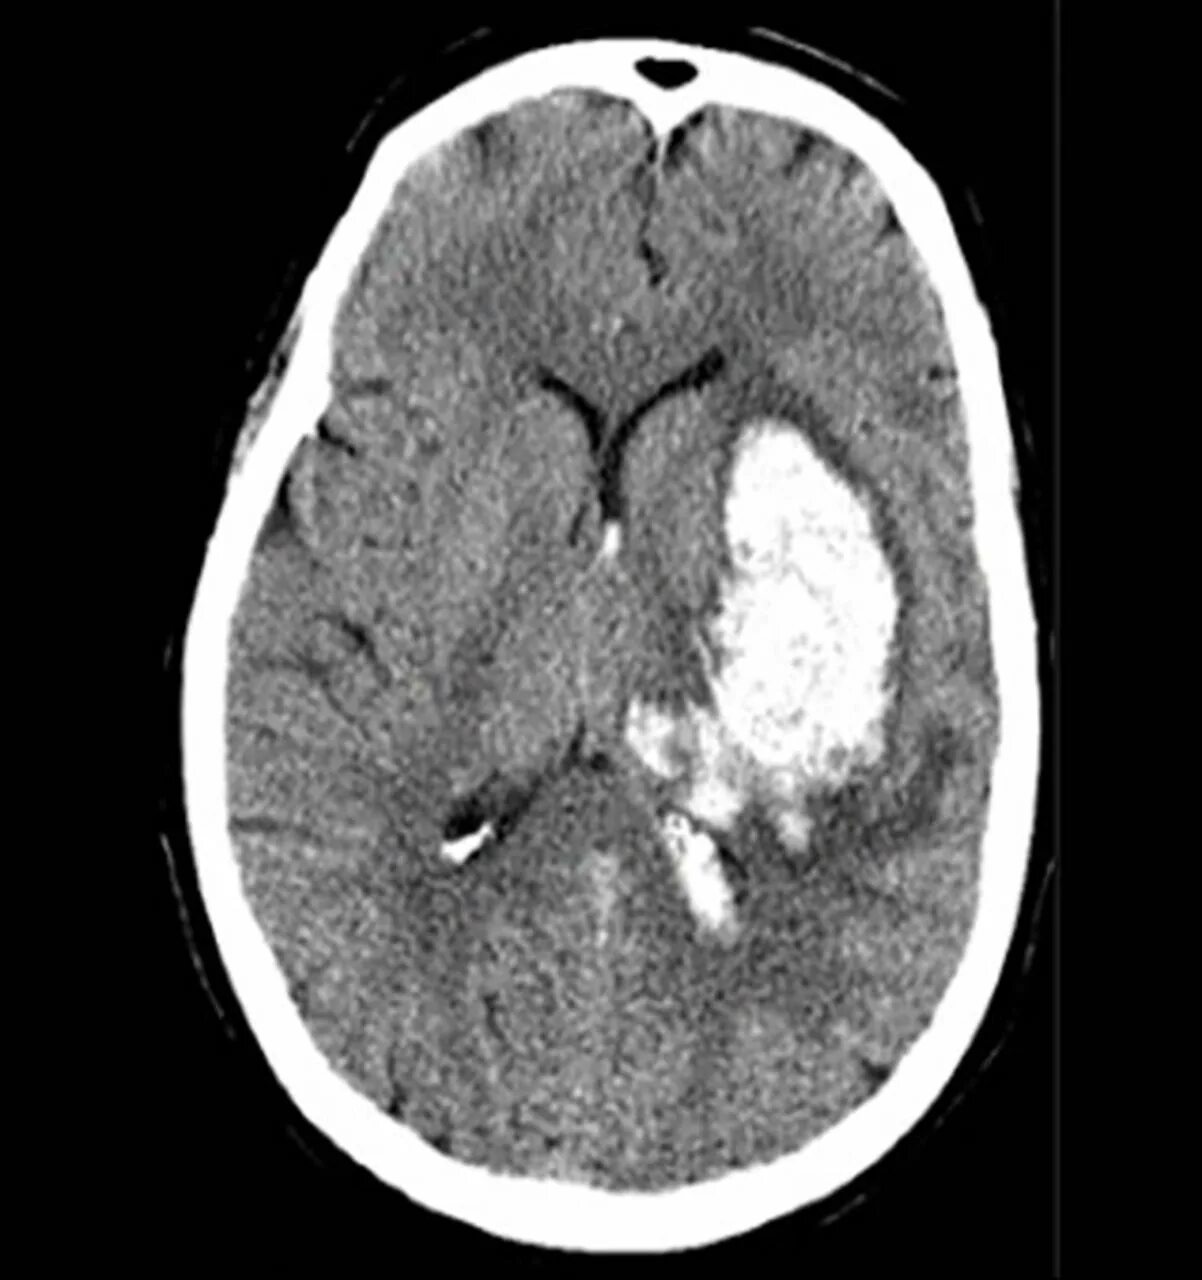

Лопнул сосуд в головном